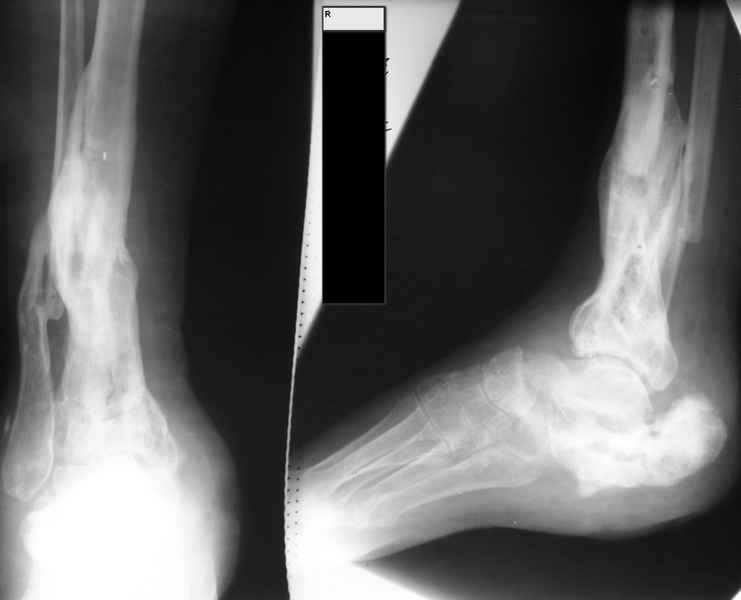

Молодая девушка со сросшимися многооскольчатыми переломами пяток и голеней.Young girl with fractures of the calcaneus Больная Н., 25 лет, падение с высоты (2008 г.). Жалобы на боли в области голеностопных суставах, в области пяток при ходьбе. Лечилась в аппаратах внешней фиксации по поводу открытых оскольчатых переломов обеих голеней, переломов пяток. Далее по поводу несросшихся переломов голеней –ЧКОС аппаратами внешней фиксации. Переломы срослись, аппараты демонтированы весной 2010г. В левой пяточной области в месте проведения спицы имеется сукровичное отделяемое. При ревизии гноя нет. Чем помочь девушке?

Patient N., age 25, falls from heights (2008). Complaints of pain in the ankles, in the heel when walking. She was treated by external fixation on open comminuted fractures of both legs, fractures of the calcaneus. Then she was treated by external fixation from nonunion of both legs. Now fractures are fused, apparatuses removed in the spring of 2010. How to help a girl?

я бы начал с осевых снимков голени (как минимум. лучше всей конечности) и фото ноги, несмотря на жутковатую картину пятки, подобные пациенты часто неплохо компенсированы (сам такой), возможно беспокоят не столько пятка. сколько деформация голени